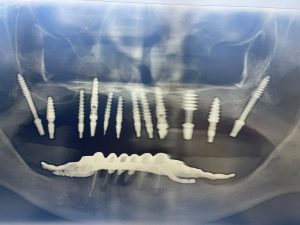

implanturi_rapide_dr_cristian_iovan_1